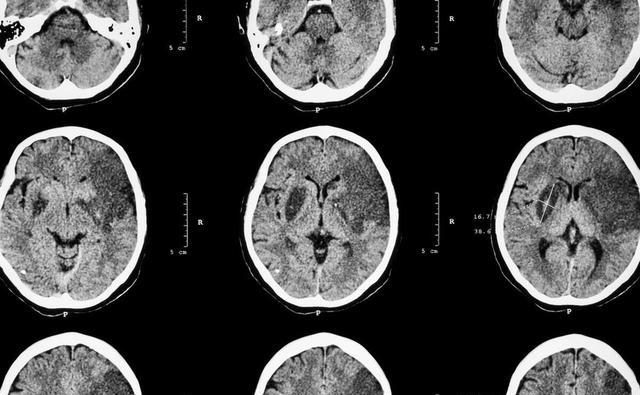

一名42岁的男子突然罹患了急性脑梗死,并住进了重症监护室,家属难以理解,一个平时身体健康的人,一个从来不喝酒吸烟的人,为什么会突然罹患脑梗呢?

在仔细询问男子的病史之后,医生发现了4点原因。